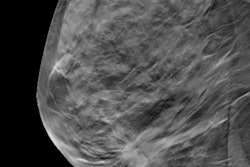

While DBT is increasingly used in breast cancer screening and may help improve cancer detection, this means higher imaging volumes for breast radiologists to interpret. This, in turn, may inadvertently contribute to burnout, with reader fatigue having negative consequences in patient care.

The team included 45 National Health Service (NHS) mammography readers from six hospitals who read a cancer-enriched set of 40 DBT cases. The readers had an average of 10 years of post-training breast experience and took an average of 105.8 minutes to report all cases. Of the study population, 21 readers had a reporting break that averaged 7.6 minutes while the remaining 24 did not. The readers also completed subjective fatigue questionnaires before and after the reporting session.